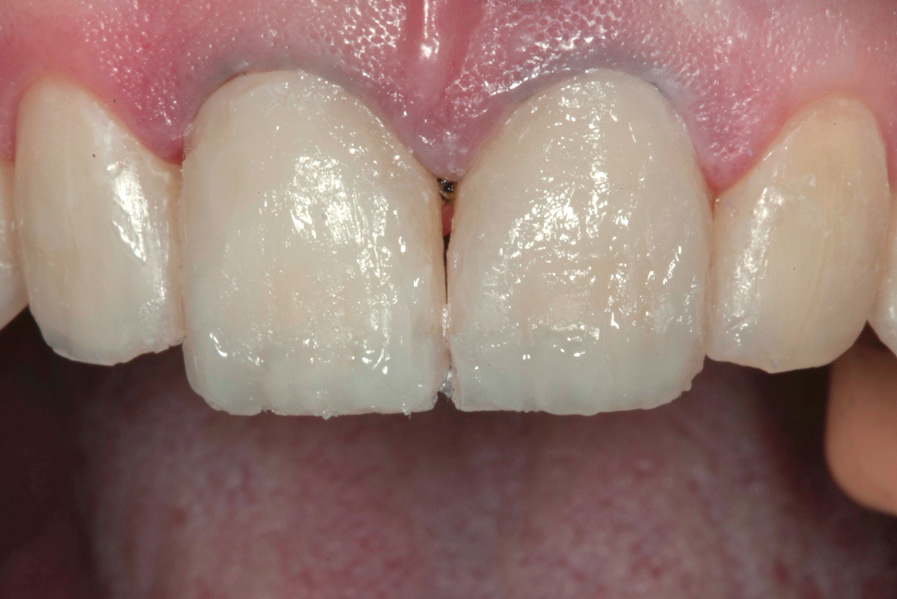

(10.) Postoperative smile photograph.

Figure 10

After the composite veneers were finalized, impressions were taken for a monolithic lithium disilicate crown on tooth No. 12. This was placed during a subsequent appointment, and occlusal equilibration was carried out. The patient returned for final photographs a couple of weeks later (Figure 10 through Figure 14).